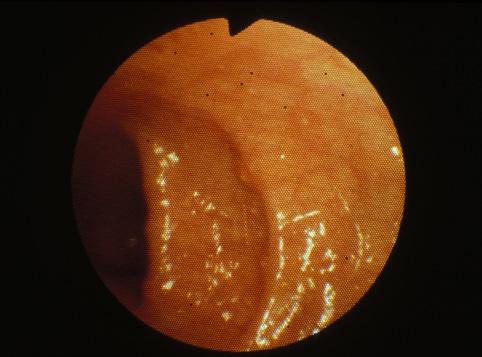

疾患(病理主体)の分類炎症性・潰瘍性疾患/アメーバ赤痢

部位(臓器別)大腸/直腸

検査方法内視鏡